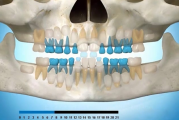

Normaalse jäävhammaskonna pilt küljelt ja eest vaadatuna.

Normaalne lõikumise järjekord 7,5-aastselt: